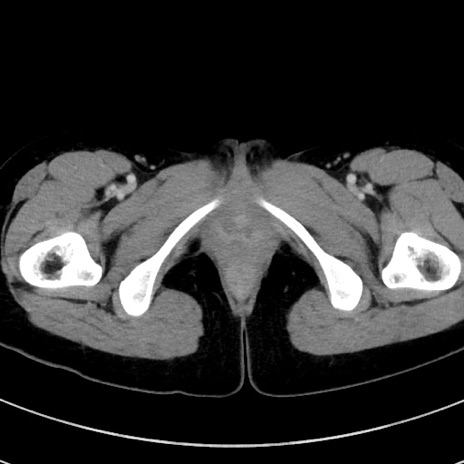

症例17(横断像)

【症例】20歳代女性

【主訴】嘔吐、下腹部痛

【現病歴】昨日夕食後に嘔吐し下腹部痛が出現。本日になっても嘔吐持続し改善しないため来院。

【身体所見】意識清明、BT 37.2℃、BP 108/67mmHg、腹部:平坦、やや硬、下腹部正中から右にかけて圧痛あり、反跳痛軽度あり、tapping pain(+)。

【データ】WBC 13600、CRP 14.94